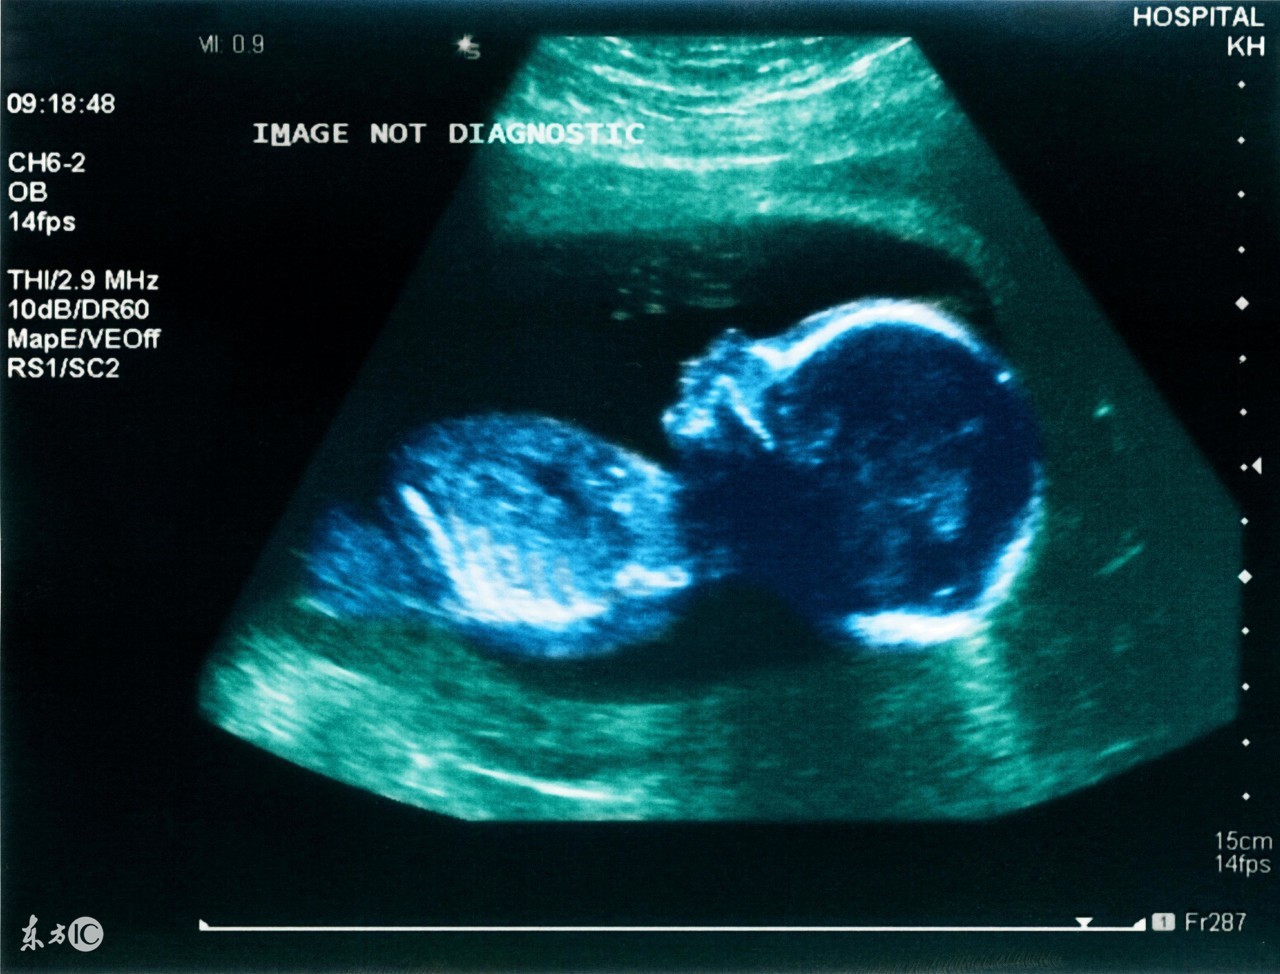

周力学介绍,这是目前国内外使用最广泛、最安全的胎儿影像学检查,可以观察胎儿大小、胎位、胎动、胎盘及羊水情况;还可以进行胎儿畸形筛查和血流动力学检测。随着科技的发展,当宝宝还未出世的时候,妈妈就可以通过三维和四维超声来观赏一下宝宝的小脸了。

早期产前超声发现了有心管搏动的胚芽后,准妈妈们可以准备预约第二次产前超声(孕13+6周III级彩超检查)了,这次时间位于停经11-13+6周。早期,这项检查的出现主要通过测量宝宝颈项透明层(也就是大家听得比较多的NT)和胎儿鼻骨来进行宝宝染色体疾病的筛查。目前这项检查也包含早期胎儿畸形的筛查及诊断,例如无脑儿、联体双胎、露脑畸形、各种常见的胎儿心脏畸形、肾脏缺如等。

完成了13+周产前III级彩超检查,又过了一个关卡的准妈妈们可以开始预约第三次产前超声(中孕产前III级彩超检查)了,也就是俗称的大排畸,也是很多准妈妈心心念念的三维检查。这项检查一般合适时机位于18周-24周。太小了宝宝还没发育好,检查价值不能完全达到,太晚了宝宝又比较大了,有的位置看得不太好,最佳时间一般位于21周-24周。这个阶段由于宝宝大部分器官已经发育,结构也比较清晰,可以进行的大部分器官结构筛查,可以排除大部分复杂胎儿畸形。